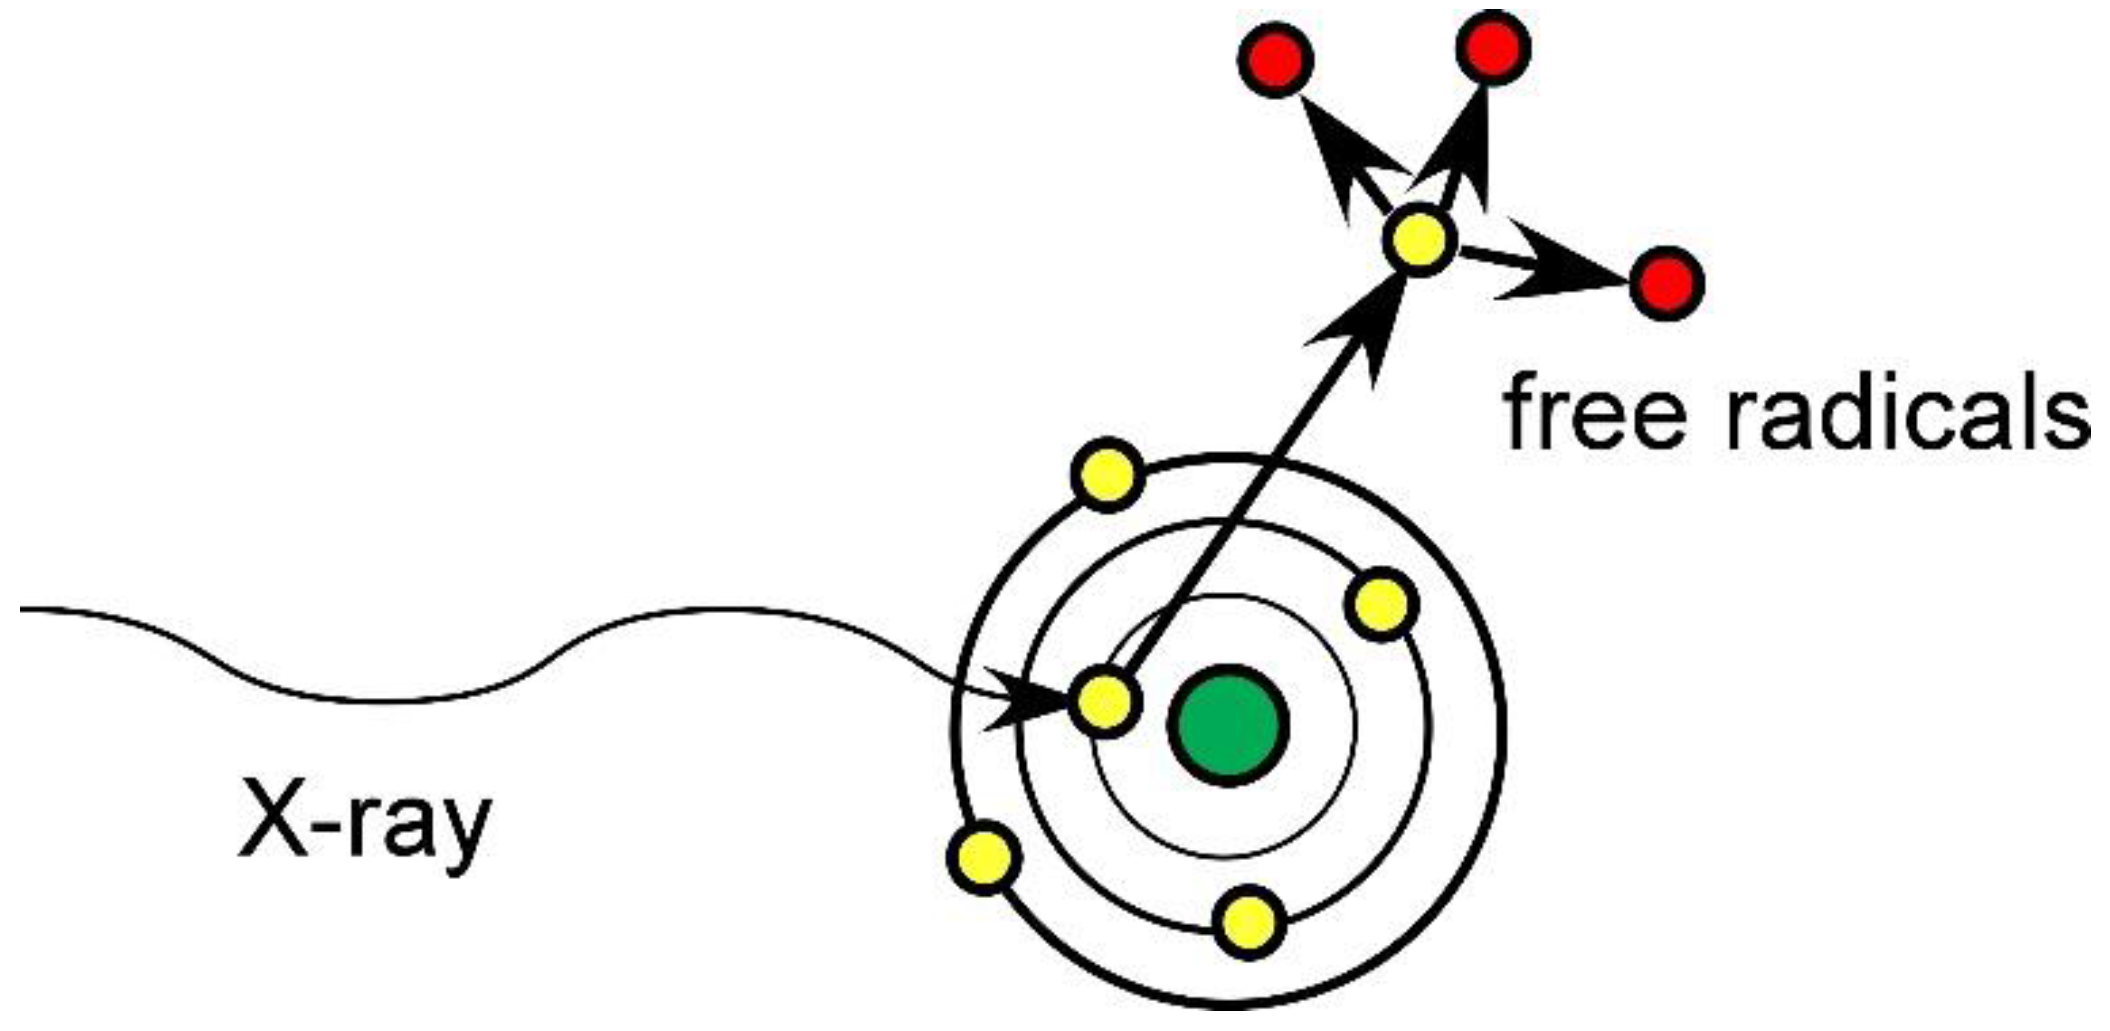

1.1. Mechanism